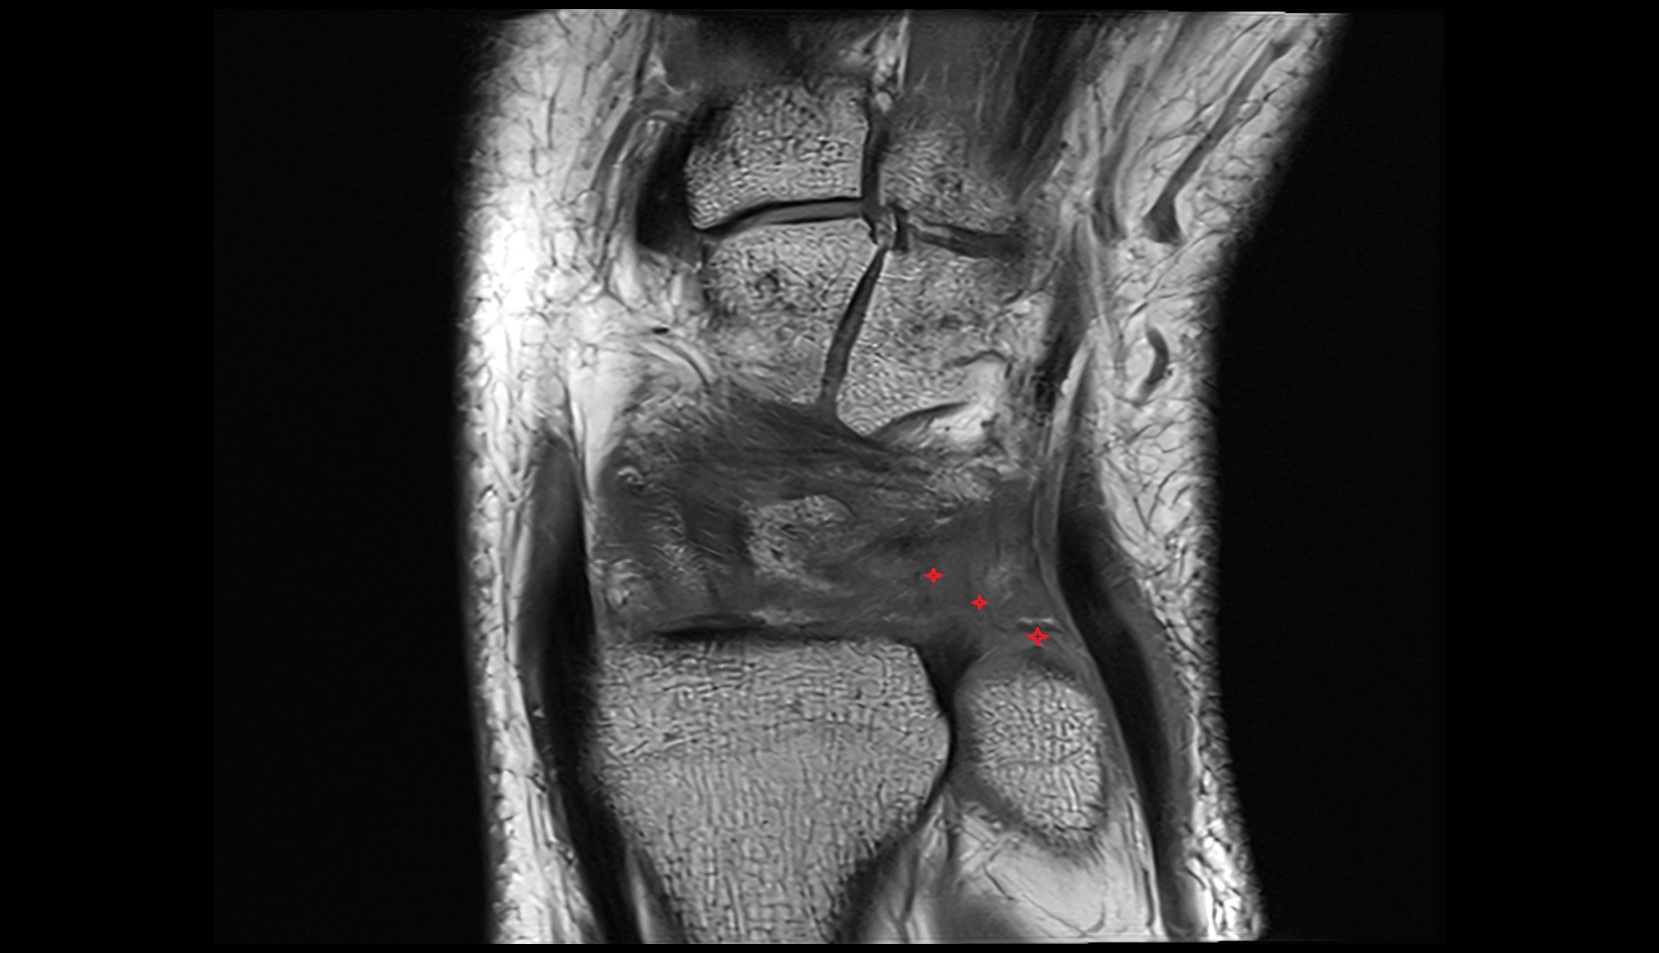

- Meniscus cartilage

- Medial meniscus

- Lateral meniscus

- Anterior horn of medial meniscus

- Posterior horn of medial meniscus

- Body of medial meniscus

- Anterior root of medial meniscus

- Posterior root of medial meniscus